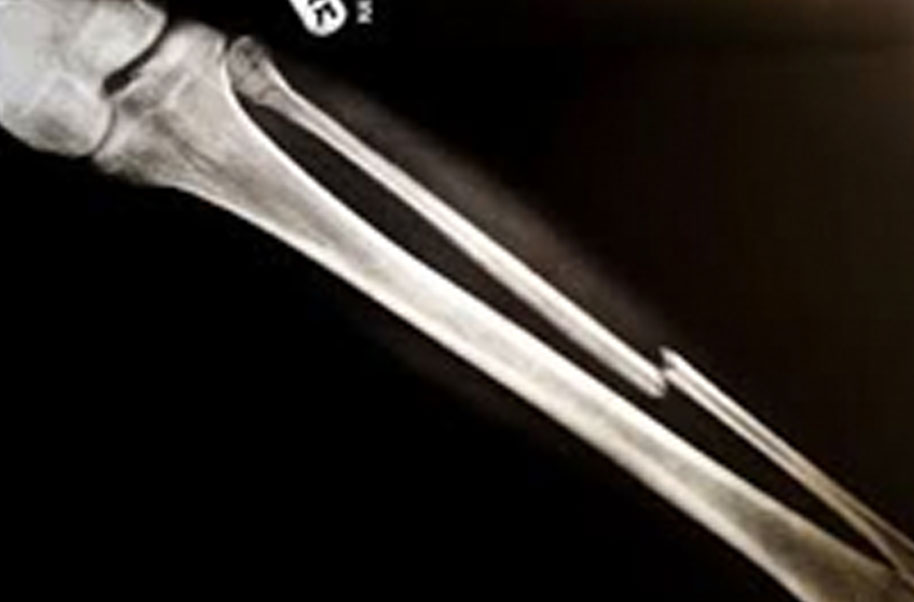

Os Longom (Broken Bone)

A complete or partial break in a bone.

- Treatment often involves resetting the bone in place and immobilising it in a cast or splint to give it time to heal. Sometimes, surgery with rods, plates and screws may be required.

Causes of bone fractures include trauma, overuse and diseases that weaken bones.